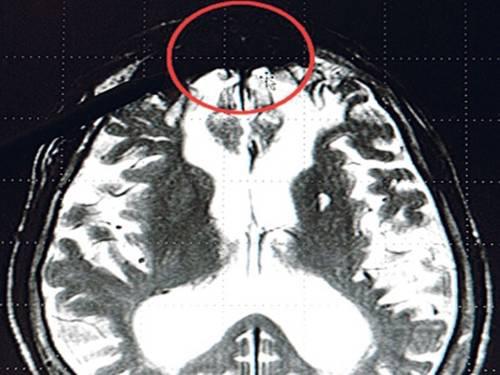

Hasil kajian ahli neurologi Jerman berjaya

menemui bahagian otak yang membuat manusia menjadi jahat. Dr Gerhard

Roth berkata, bahagian itu terletak di depan bawah otak manusia yang

kelihatan seperti tompok hitam melalui pemeriksaan X-ray.

“Tompok hitam itu ditemui pada hampir setiap pelaku jenayah,” katanya sebagaimana yang dilaporan Sinar.

Beliau menemuinya ketika membuat kajian tentang pelaku jenayah di Jerman yang dipenjarakan untuk tempoh lama. Penyelidikan tersebut menunjukkan perilaku jahat juga boleh diwarisi daripada genetik.

“Jika terdapat ahli keluarga mempunyai penyakit di bahagian hadapan otaknya, sebanyak 66 peratus generasi berikutnya berpotensi mengalami simptom sama,” jelasnya lagi.